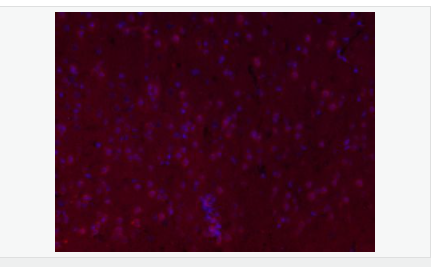

交叉反應(yīng):Mouse,Rat(predicted:Human,Pig) 推薦應(yīng)用:IHC-P,IHC-F,IF,ELISA

產(chǎn)品應(yīng)用ELISA=1:5000-10000 IHC-P=1:100-500 IHC-F=1:100-500 IF=1:100-500 (石蠟切片需做抗原修復(fù))

FSCN1為細(xì)胞骨架肌動(dòng)蛋白的一種,該蛋白有蛋白結(jié)合,橋連、肌動(dòng)蛋白絲結(jié)合的功能。 主要參與細(xì)胞增殖、肌動(dòng)蛋白細(xì)胞骨架組織和生物發(fā)生、肌動(dòng)蛋白絲束形成。Fascin也是一種actin結(jié)合蛋白,它的功能是把F-actin聚集捆綁成束,與細(xì)胞的運(yùn)動(dòng)相關(guān)。病理情況下,各種惡性腫瘤細(xì)胞經(jīng)常高表達(dá)Fascin。